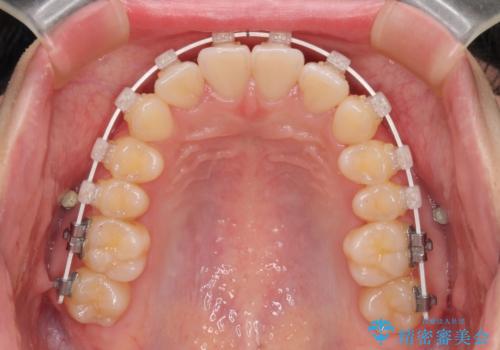

- 矯正装置

- 審美装置

- 1年1ヶ月

- 10-30回

- 上下前歯のデコボコを気にして来院された患者様です。

ワイヤー矯正でもマウスピース矯正でも可能でしたが、短期間で、自身の手を煩わせることなく治療を行いたいとのことで、ワイヤー装置にて矯正治療を行うこととしました。

舌の突出癖により、出っ歯仕上がりとなる可能性がありましたが、舌のトレーニングを頑張っていただき、1年強で終えることができました。